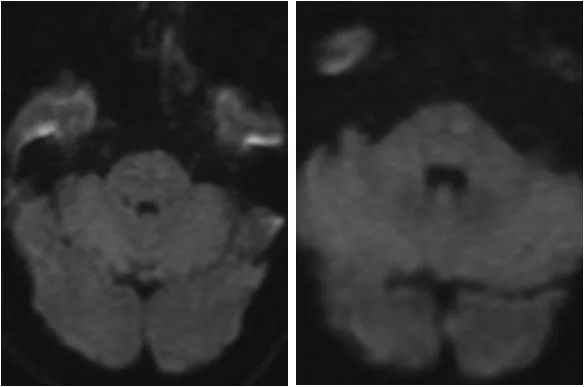

患者20余天前感右上肢麻木无力,因程度轻,未予重视。10余天前出现头晕,伴站立不稳,持续约1分钟后自行好转。病后就诊当地医院行头MRI:脑桥区新鲜梗死(图1)。

图1

MRA:双侧胚胎型大脑后动脉;左椎动脉优势,V4段重度狭窄(图2)。